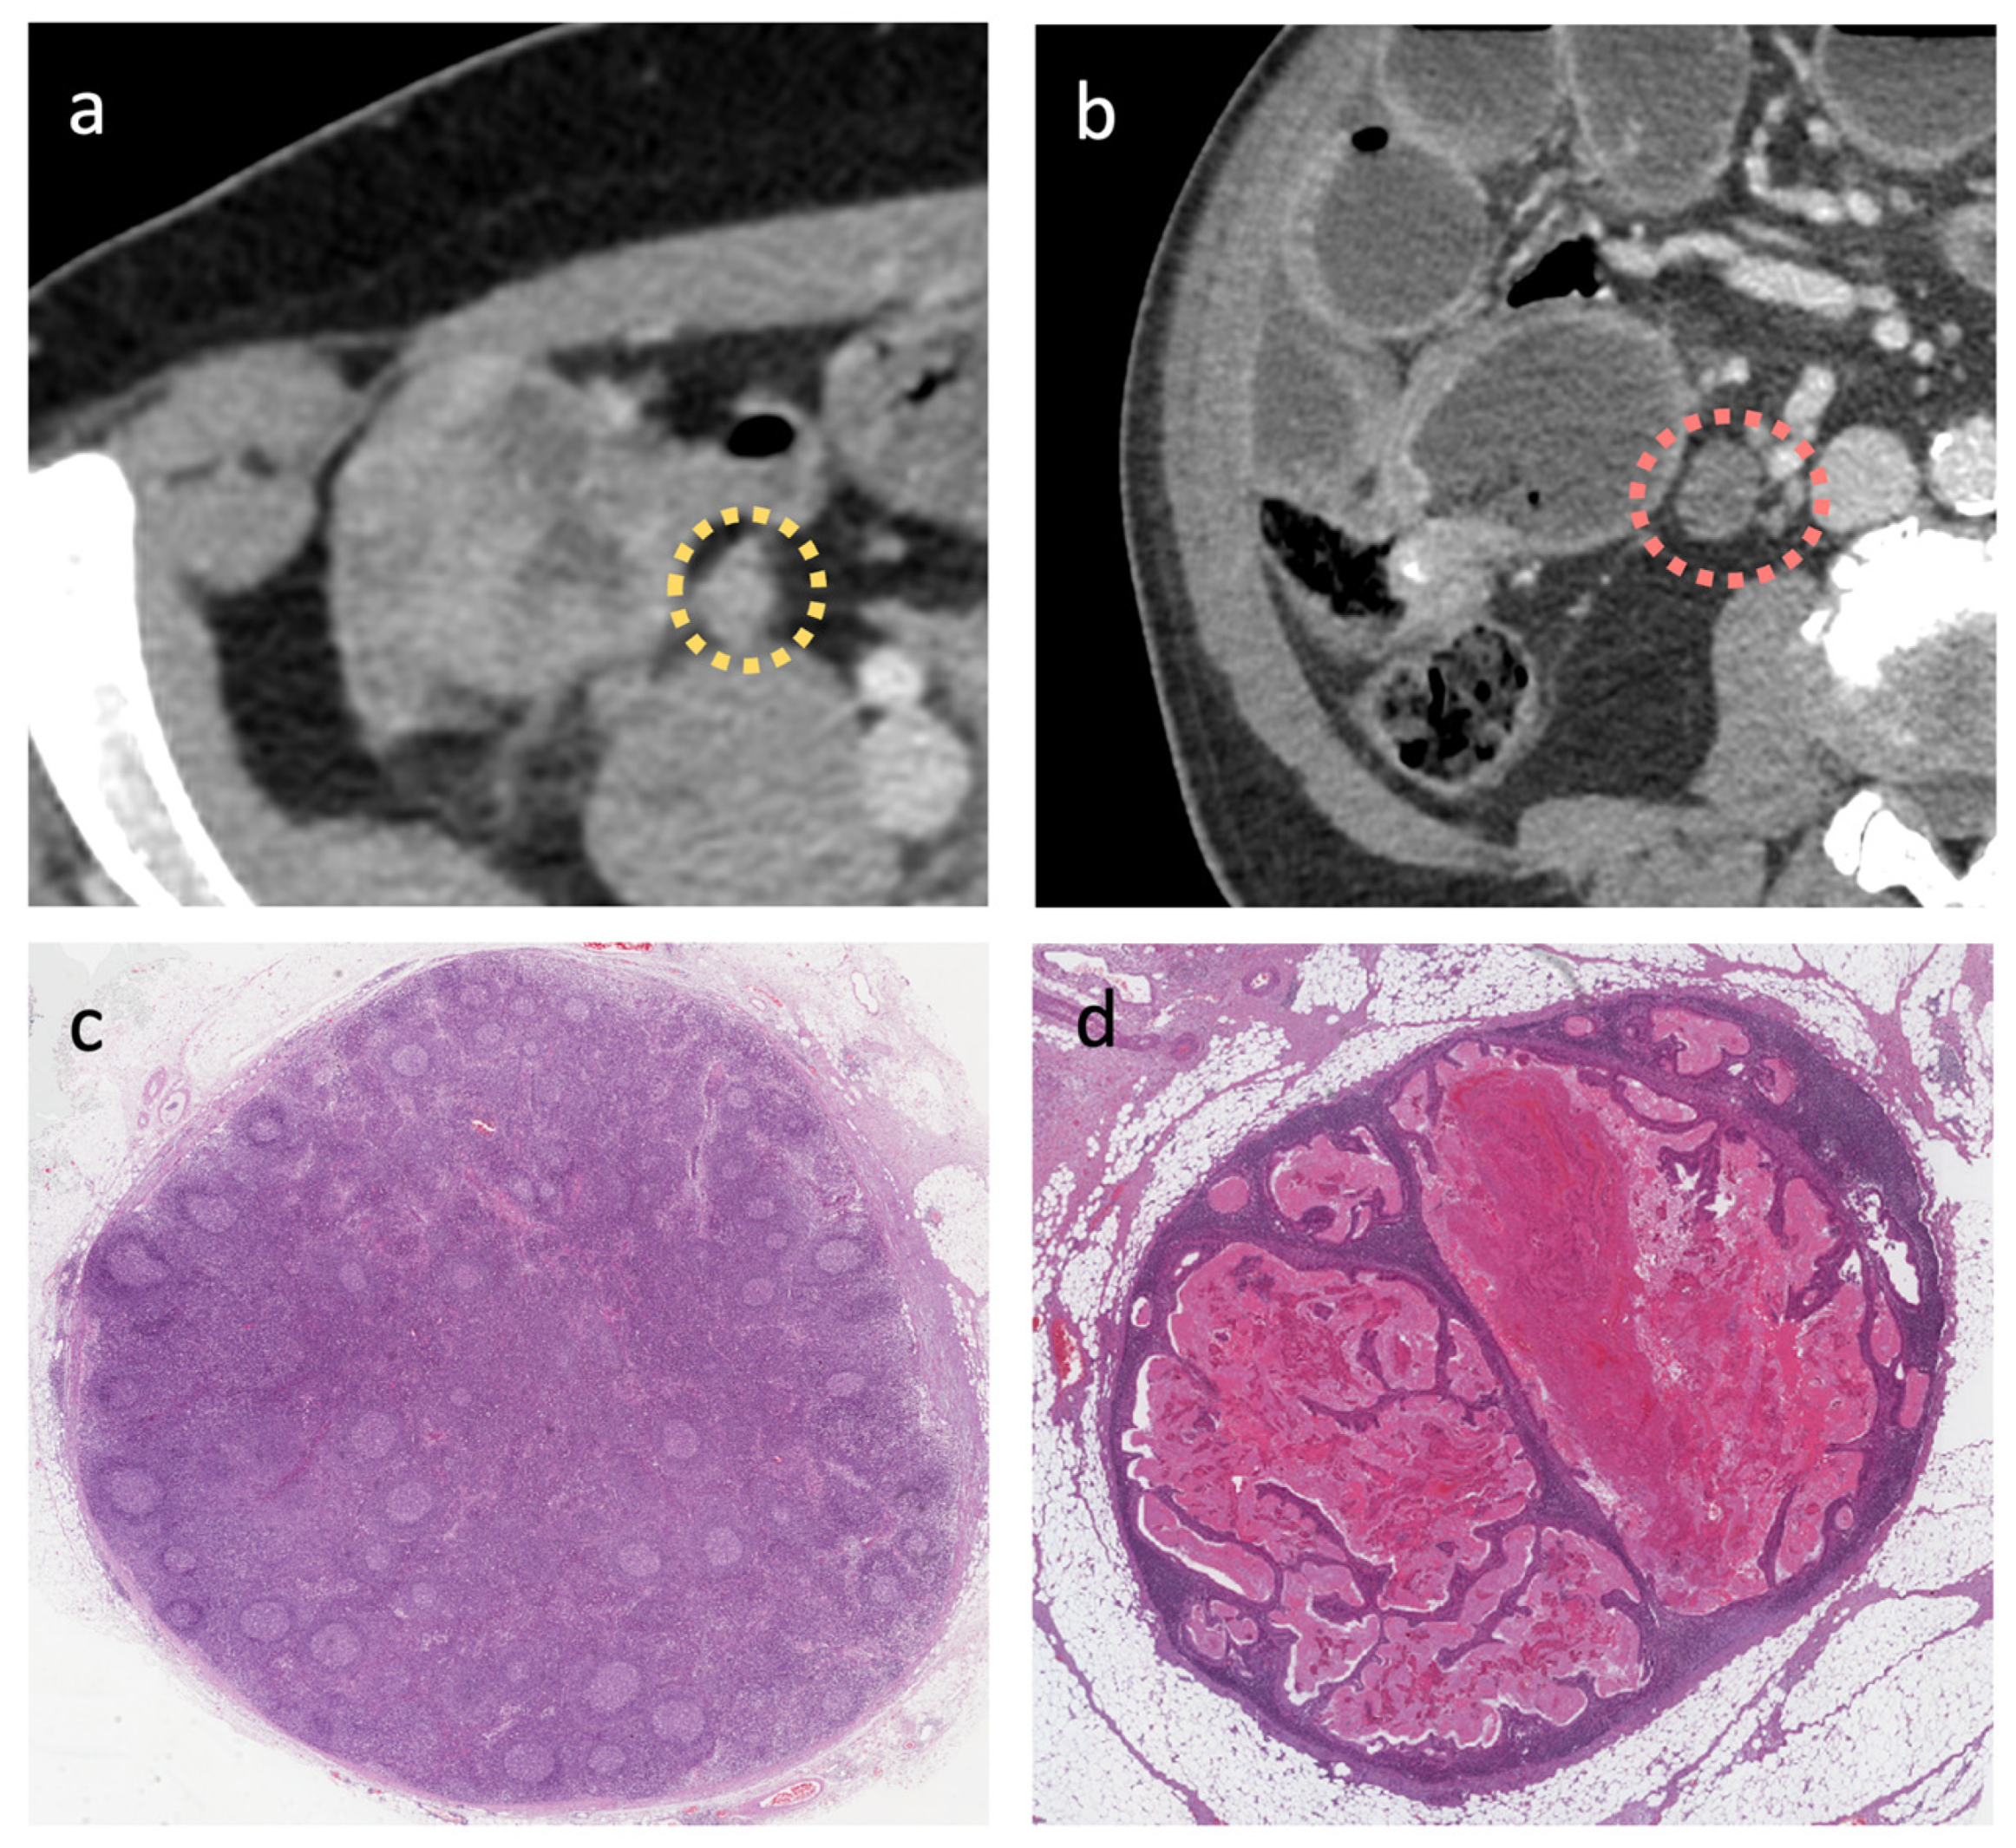

2.3. CT Scan Morphological Analysis

3.2. NODE-SCORE

3.3. D Segmentation and LN’s Radiomic Features